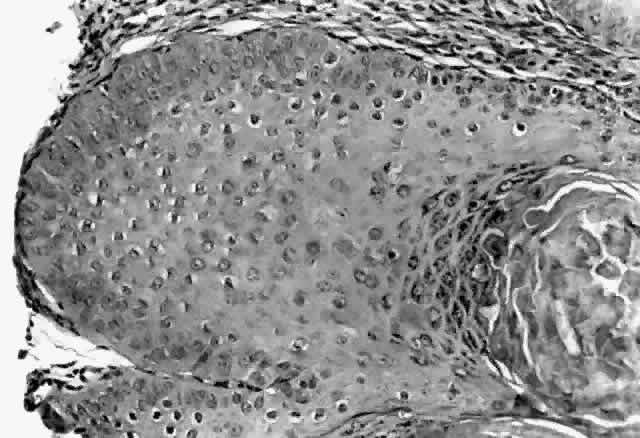

HPV-induced conjunctival squamous papillomas demonstrate papillomatosis, acanthosis, and koilocytosis (Fig. 6). Because they are mucous membrane lesions, those of the conjunctiva and lacrimal sac show no granular cell layer but will show keratinization if they are large or exposed (Fig. 7). In our experience the frequency of koilocytes is variable, even in lesions almost certain to be viral (Fig. 8). Scattered inflammatory cells may be present in the cores or epithelium. Virus can be detected immunohistochemically in the nuclei of the cells (Fig. 9).

|

|

Early dysplastic lesions (conjunctival intraepithelial neoplasia) show thickened epithelium with extension of basal-like cells beyond the basal layer, but cells continue to mature into flat squamous cells. Mitoses are also seen higher in the epithelium. As the degree of dysplasia worsens, the more superficial epithelium is replaced at higher levels by basal-type cells, mitoses can be seen further from the basal layer, and atypia of cells becomes more pronounced. With squamous cell carcinoma in situ, there is full-thickness dysplasia, cellular atypia is variable, and mitoses can be seen at all layers of the epithelium. Invasive squamous cell carcinomas are usually well differentiated. Pleomorphism, hyperchromaticity, dyskeratosis, and horn pearls are seen. Epithelial cell clusters can be seen invading below the basement membrane. Inflammatory cells are common in the substantia propria.

Squamous papillomas of the eyelid are exophytic lesions with multiple fronds, each showing acanthotic epithelium around a fibrovascular core. There is typically hyperkeratosis and koilocytosis. Inflammatory cells may be present.